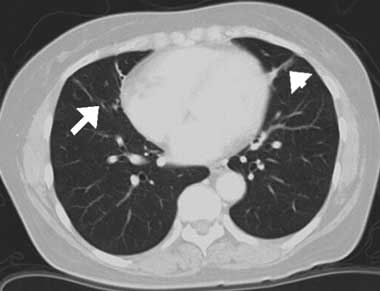

A diagnosis of middle lobe syndrome secondary to Sjögren’s syndrome was made and the patient was initially treated with methylprednisolone (125 mg/day for 4 days), followed by prednisolone (20 mg/day). The glucocorticoid dose was tapered off as the atelectatic lesions resolved. A repeat CT scan performed 1 year later showed that the atelectatic lesions had almost completely disappeared with this treatment (Box, D). Subsequently, the prednisolone dose was ceased.